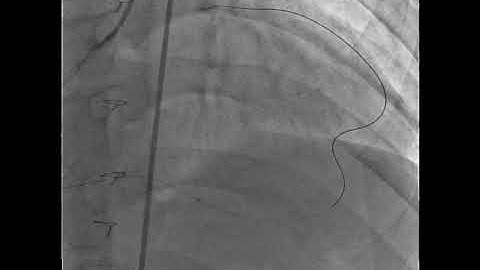

Megaly_Stent loss during LAD CTO PCI_Coronary